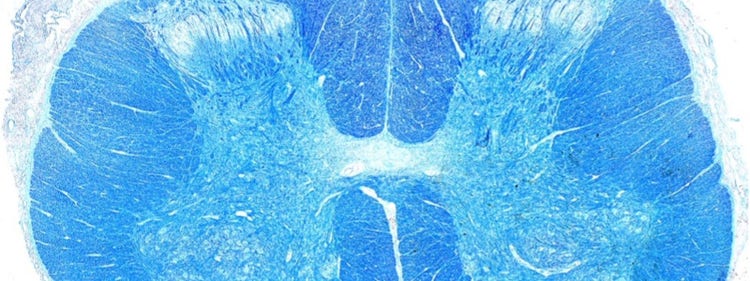

Stephanie Shiers博士による研究誌の表紙作品

Science Translational Medicine(vol. 14, issue 632)の表紙を飾ったStephanie Shiers博士の作品(AAASの許可を得て転載)。